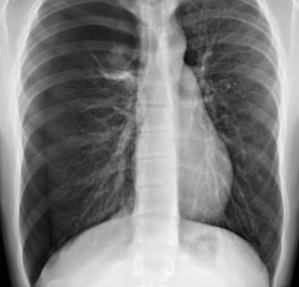

14

Q

¿Cuál es el dx?

A

Carcinoma broncogénico